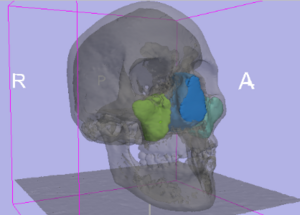

Range of Curvilinear Distraction Devices Required for Treatment of Mandibular Deformities

Publication: J Oral Maxillofac Surg. 2006 Feb;64(2):259-64.

Authors: Ritter L, Yeshwant K, Seldin EB, Kaban LB, Gateno J, Keeve E, Kikinis R, Troulis MJ

Institution: Department of Oral and Maxillofacial Surgery, Massachusetts General Hospital, Boston, MA, USA.

Background/Purpose: The purpose of this study was to determine the range of fixed trajectory curvilinear distraction devices required to correct a variety of severe mandibular deformities. MATERIALS AND METHODS: Preoperative computed tomography (CT) scans from 18 patients with mandibular deformities were imported into a CT-based software program (Osteoplan). Three-dimensional virtual models of the individual skulls were made with landmarks to track movements. An ideal treatment plan was created for each patient. Upper and lower boundaries for the dimensions of curvilinear distractors were established based on manufacturing and geometric constraints. Then, anatomically acceptable distractor attachment points were identified on the models using proximal and distal grids. Treatment plans were simulated for a series of distractors with varying radii of curvature, elongations (arc-length of device), and placements along the grids. The outcomes using these distractors were compared with the ideal treatment plans. Discrepancies were quantified in millimeters by comparing landmarks in the simulated versus ideal movements. RESULTS: Approximately 400,000 simulated 3-dimensional movements, based on the distractor parameters and variations in placement were computationally evaluated for the 18 cases. It was determined that, by varying distractor placement, a family of 5 distractors, with 3, 5, 7, and 10 cm radii of curvature and a straight-line device, could be used to treat all 18 cases to within 1.8 mm of error. CONCLUSIONS: The results of this study indicate that a family of 5 curvilinear distractors may suffice to treat a broad range of mandibular deformities.